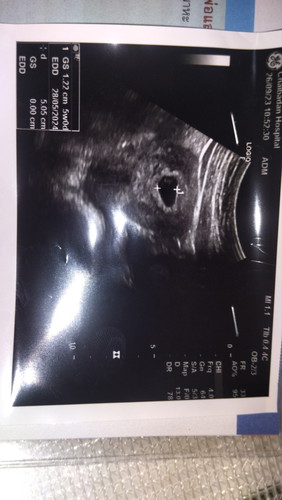

ตรวจครรภ์ไม่เจอตัว

คุณแม่บ้านไหนตรวจน้องเจอกี่วีคค่ะเราไปตรวจตอน8วีคพอดียังไม่เจอตัวน้องเลย ภาวนาขอไห้น้องมีตัวคุณหมอนัดอีก2อาทิตมาตรวจว่ามีตัวไหม #ขอบคุณล่วงหน้านะคะ #ท้องแรกคะ

บ้านนี้ 7 สัปดาห์ ไม่เจอตัวน้องเหมือนกัน เจอแต่ถุงตั้งครรภ์ ต้องรออีก 4 สัปดาห์คุณหมอให้ไปตรวจใหม่ แอบกังวลอยู่เหมือนกัน 😢